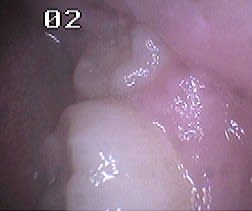

Un autre type d'application en paro du CO² est son utilisation sans photo-ablation en défocalisant à faible puissance, ce qui entraine une cautérisation avec stérilisation, décongestionnement par évaporation de l'inflammation, sédation immédiate des douleurs et biostimulation.

Un exemple la semaine dernière: une patiente de 21 ans reçue en urgence pour un accident d'éruption de la 38 ayant entrainé une névralgie et un trismus avec ouverture limitée à 22mm.

Après utilisation d'un diode HeNe AsGa en mode myorelaxation, ce qui a permis une ouverture en quelques secondes à 30mm, un tir en balayage continu du CO² à 1W a fait disparaitre instantanément la douleur et a porté l'ouverture buccale à 40mm. Le tout a pris seulement quelques minutes.

J'ai alors pu lui prendre une radio et ai poursuivi sans problème par son premier détartrage, la jeune fille étant fumeuse (10 cigarettes par jour depuis 2 ans)... je suis alors tombé sur des leucoplasies au maxillaire que je n'aurai jamais découvertes sans l'aide de mes lasers ou avec une prescription d'AB et AI sans la revoir probablement, ses dents étant impeccables.

Je les lui ai montré et ai essayé de lui faire prendre conscience des risques qu'elle prenait en continuant à fumer sans l'affoler évidemment.